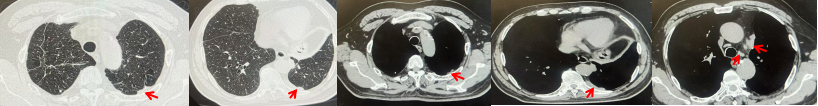

69岁男性,无糖尿病、高血压、心脏病等基础疾病,无吸烟、饮酒史,无肿瘤家族史。2023.06.07行胸部CT检查:右肺上叶胸膜下见肿物影,大小约33mm×22mm,边缘可见分叶,考虑恶性病变可能性大,双肺间质改变(如图1)。2023.06.14行“单孔胸腔镜下右肺上叶切除、肺门及纵隔淋巴结清扫、胸膜粘连松解术”;术后病理:(右肺上叶)腺癌(低分化,实体型占60%,不良腺体占40%),局灶伴神经内分泌标记表达(CD56、Syn),可见STAS及胸膜侵犯,未见确切神经侵犯及脉管内癌栓;(气管切缘)净;(淋巴结)未见转移癌0/26(2组0/2;4组0/6;7组0/2;对侧7组0/8;10组0/2;11组0/3;12组0/2;13组0/1)。术后分期pT2aN0M0 IB期,术后NGS基因检测:无驱动基因突变,PD-L1(22C3)TPS<1%。术后定期复查。

图1:患者手术前(2023.06)胸部CT肺窗及纵隔窗